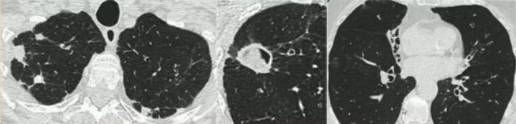

单纯肺曲菌球:非免疫受损病人,有较少或没有症状,含真菌球单发空洞,具有曲霉菌血清学和微生物学依据(阳性结果),至少观察3个月没有放射影像学的进展。

曲霉结节:不常见,单发或多个结节(<3cm),有或没有空洞,常出现坏死,但不表现为组织侵袭。易与结核、肺癌、肺球孢子菌及其他疾病混淆,只能依靠组织学明确诊断。

亚急性侵袭性肺曲霉病(SAIA):轻度免疫缺陷的侵袭性肺曲霉病患者,发生在1-3个月内,具有可变的影像学特征,包括空洞、结节、有“脓肿形成的进展性实变”。最重要的特征为肺组织发现菌丝,另血液或呼吸液GM试验呈强阳性。